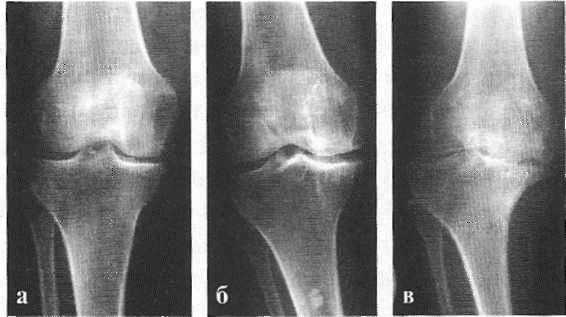

В подавляющем большинстве случаев достаточно осмотра и рентгенограммы коленного сустава в двух проекциях (прямой и боковой). [2] [19] Клинические данные и снимки позволяют определить стадию заболевания.

На ранних стадиях заболевания, при незначительных изменениях в костной ткани, рентгенологическое обследование не настолько ценно. [5] [8] На этом этапе гонартроз возможно диагностировать благодаря артроскопии. [5] [8] Точность метода очень высока, останавливать может только его инвазивный характер и цена.

- Рентгенография коленного сустава. Не позволяет оценить состояние хрящевой ткани. Назначается для исключения других патологий и выявления сопутствующих изменений костных структур: расширения суставной щели, уплощения суставных поверхностей бедренной и большеберцовой кости на стороне поражения.